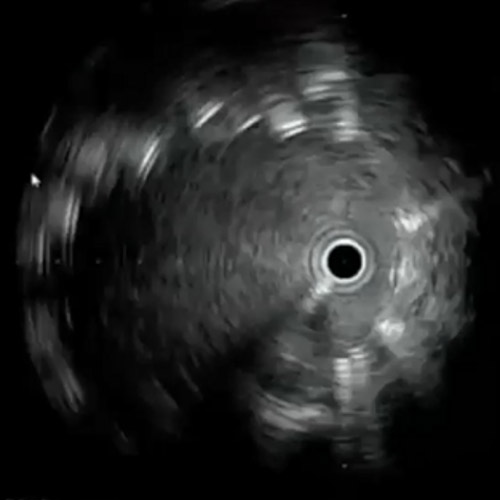

左dRAからエコーガイド穿刺を行いGlidesheateh Slender7FrとR2P SlenGuideの組み合わせでアプローチを開始した。その際、カバードステント(シャフト長135cm)の留置を予定していたため、よりガイディングカテのシステム全長を短くするためにR2P SlenGuideに止血弁を組み合わせた。R2P SlenGuideが病変部に対してコアキシャルになり難く、バックアップは十分に取れなかったが、6gワイヤー(0,014“)で病変を通過後、Navifocus WRでintra-plaque内であることを確認し、Senri 3-40mm でプレ拡張を行った(図3)(図4)。

EIAの動脈瘤部にはカバードステントを留置することにした。6gワイヤー(0.014“)のままカバードステントのデリバリーを試みるが、バックアップが弱くEIAまで到達できなかった。6gワイヤーからサポート性の高い0.018ワイヤーに交換したが、ワイヤーが末梢まで到達できなかった。ラジフォーカスガイドワイヤーMスティッフ(0.035”)に交換することでサポート性を更に高めてデリバリーをし、カバードステントがIIA入口を塞がないように出来るだけ奥までデリバリーして留置した(図5)(図6)。